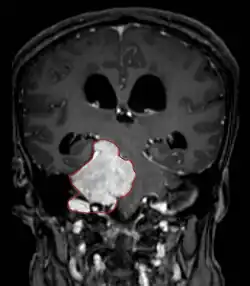

Imaging

• MRI

• Preferred imaging because it can show dural origin

• Dural tail sign seen in about two-thirds: characteristic marginal thickening that tapers peripherally along the dura

• Isointense on T1, hyperintense (usually homogeneously) on T2, strong enhancement with IV contrast